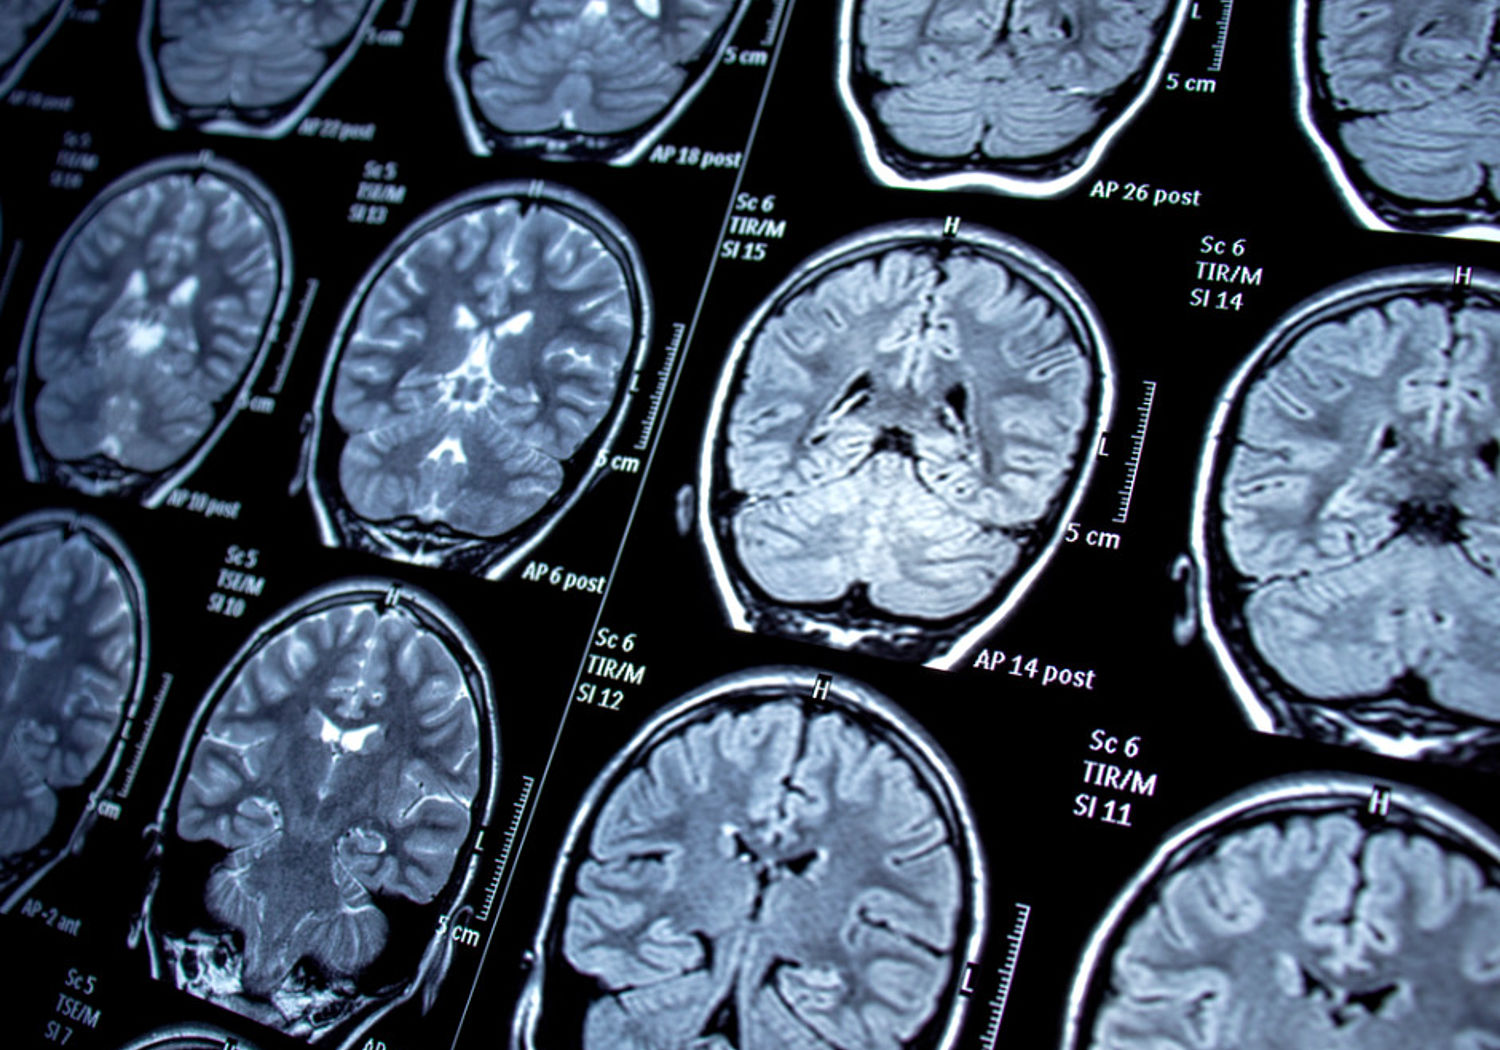

Magnetic resonance imaging (MRI) uses radio waves and large magnetic fields to help identify conditions ranging from damaged ligaments to cancer. Around 40 million MRI scans are performed each year in the EU, but the size and cost of scanners means that not all European citizens have equal access to this form of medical diagnosis.

‘Low-field MRI’ is a portable form of the standard MRI scanner, opening opportunities to provide treatment at a patient’s locality. However, these machines currently lack metrological traceability on the results they give. These instruments also lack the accredited documentation blueprints of hardware and software required by the EU’s Medical Device Regulation (EU)2017/745 (MDR).

This project will design, develop, and fully characterise a mobile, low-cost (<50 k€), low-field MRI system. For the first time, multiple low-field low-cost open-source MR scanners will be built at different sites and evaluated.